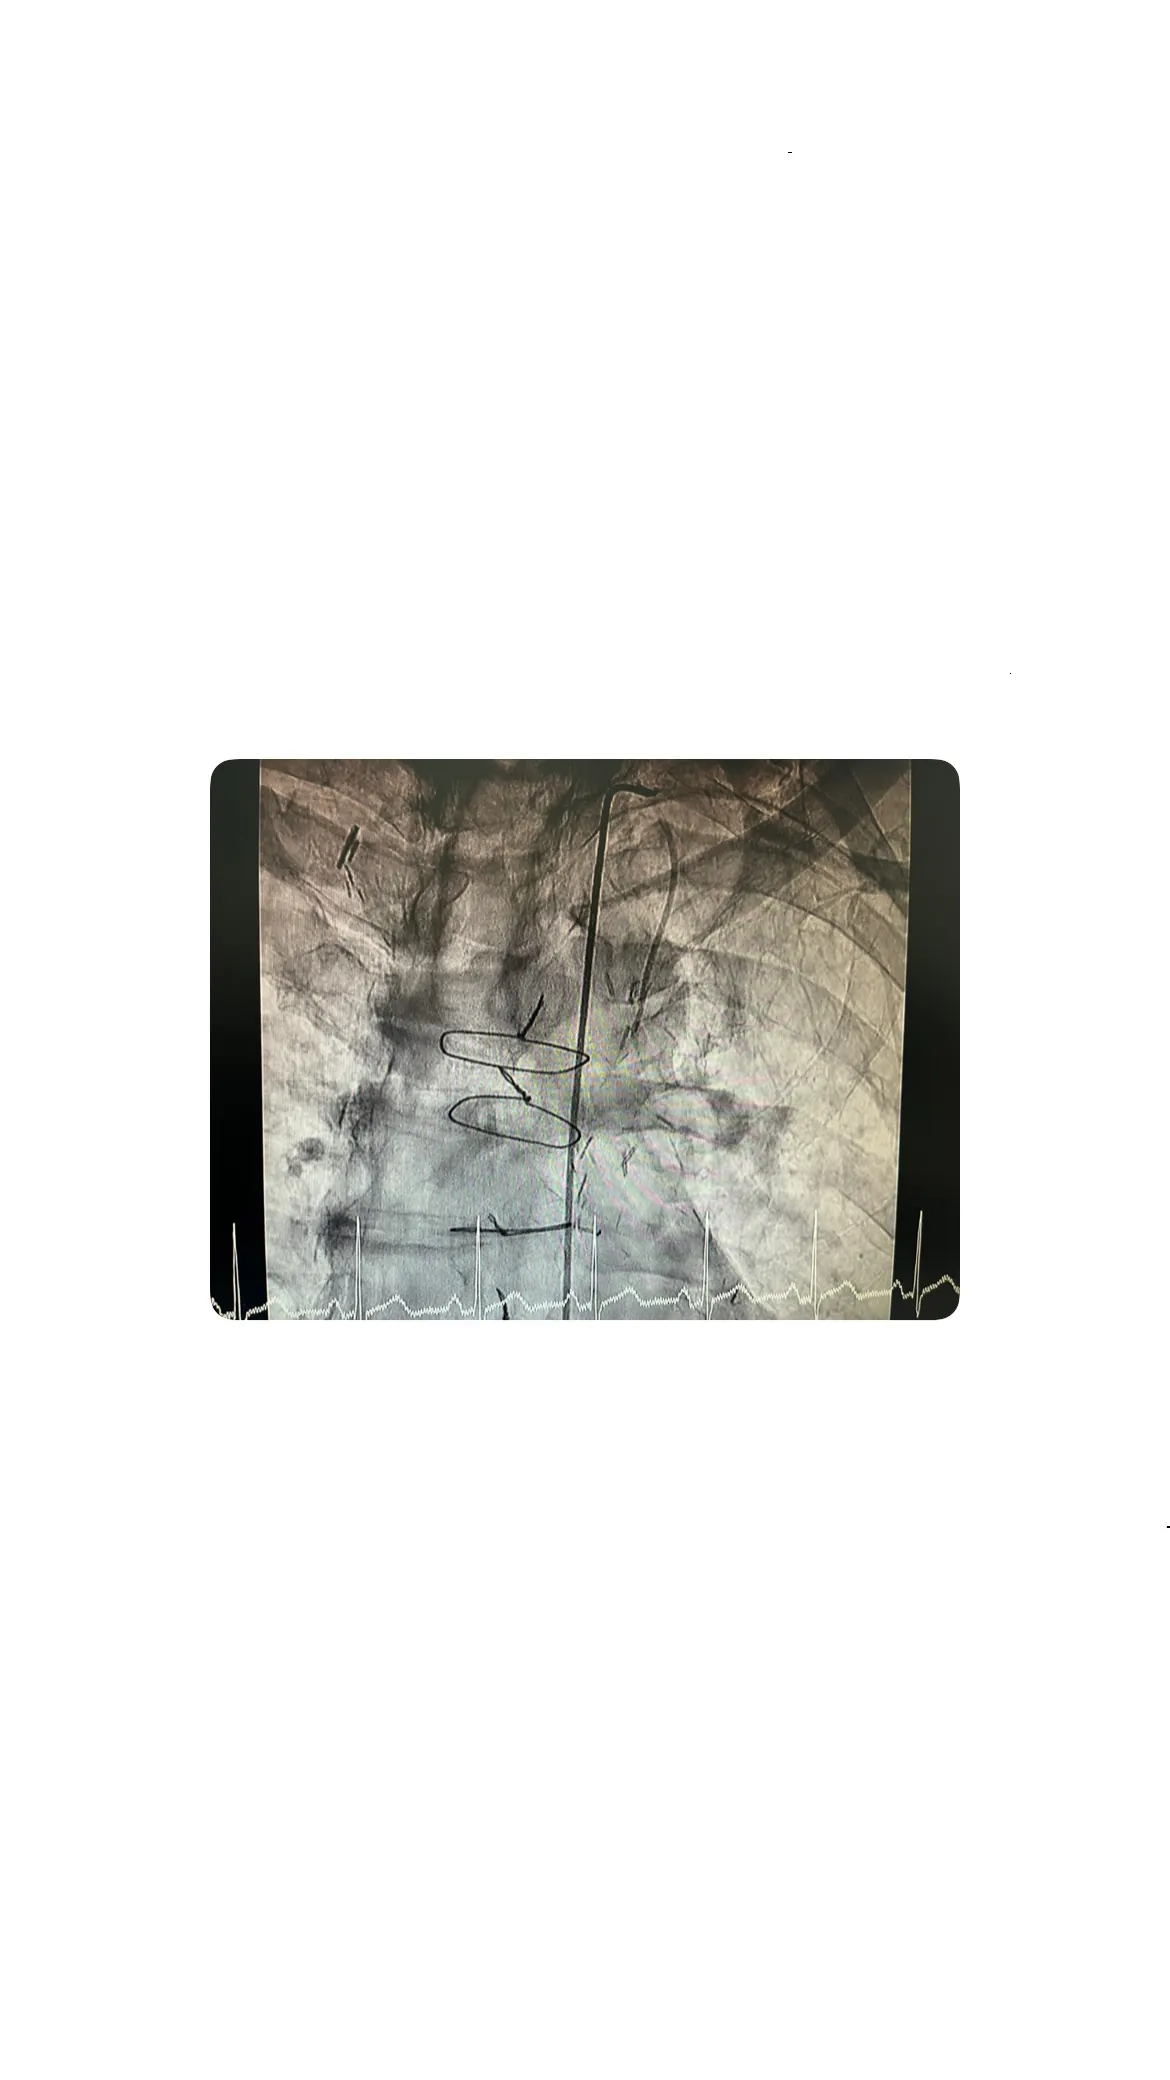

Subida del catéter y visualización del árbol coronario

Una vez que se logró el acceso a través de la arteria femoral, el catéter fue guiado hacia el corazón. Este procedimiento permitió la visualización del árbol coronario, proporcionando una imagen clara de las arterias y los bypasses. La visualización es crucial para identificar cualquier obstrucción o problema en el flujo sanguíneo que pudiera estar causando el dolor torácico del paciente.

Imágenes angiográficas: grapas, suturas y complejidad del bypass

Visualización de las grapas y la sutura de esternotomía

Las imágenes angiográficas obtenidas durante el cateterismo revelaron detalles interesantes sobre la cirugía de bypass previa. Se pudieron observar claramente las grapas utilizadas en los bypasses y la sutura de la esternotomía. Estos elementos son testimonio de la complejidad y precisión requeridas en este tipo de procedimientos quirúrgicos.